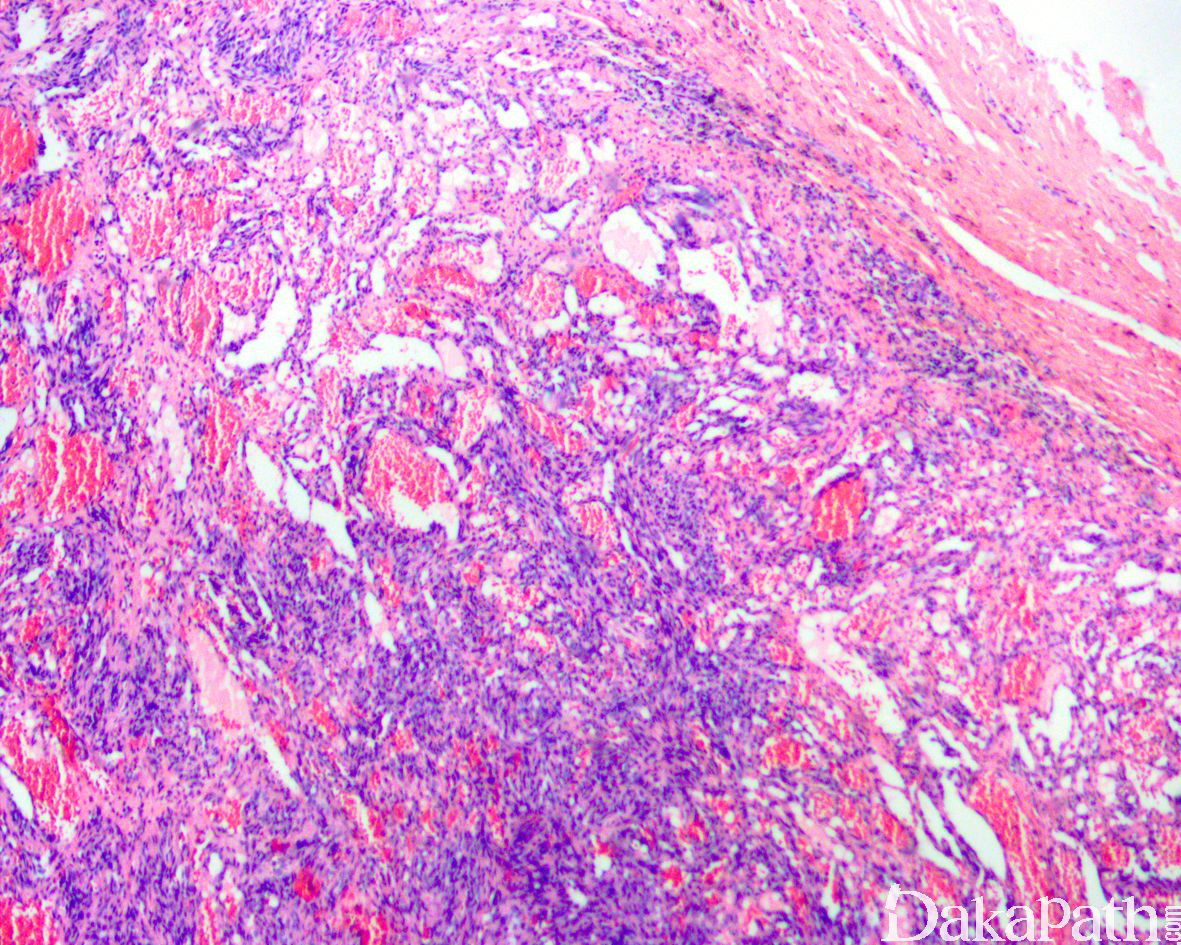

病变直径较小,通常< 2cm, 位于真皮或皮下,偶尔可位于深部软组织,组织学呈多结节状生长,主要由海绵状血管瘤样区域和实性梭形细胞区域两种成分组成,梭形细胞成分达 50%以上;

海绵状血管瘤样区域内的血管多为扩张的薄壁血管,大小不一,内衬扁平内皮细胞,常充满血液,可伴血栓形成;

实性区域梭形细胞多和海绵状血管瘤样区域相互交融,梭形细胞呈短束状排列,其中血管或为扩张的薄壁血管,或呈不规则裂隙样,间质内常可见外渗的红细胞,类似卡波西肉瘤;

约 50%的梭形细胞血管瘤可见肿瘤于血管内生长,10-20%的梭形细胞血管瘤可完全位于血管内。取决于血管瘤样成分和梭形细胞成分的比例多少,梭形细胞血管瘤在低倍镜下可能类似于海绵状血管瘤或 Kaposi 血管肉瘤;